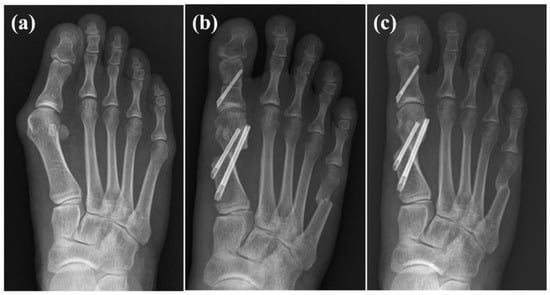

Complications were present in one patient who showed screw pull-out during follow-up, with favorable functional and radiographic outcomes. Two patients presented recurrent hallux valgus: one patient reported satisfactory surgical results along with significantly improved pain scores, while the other reported disappointing results. An example case is depicted in Figure 6.

Figure 6. Case example of female, 35-year-old patient. (a) Preoperative radiographs show moderate hallux valgus deformity; (b) 6 weeks following surgery, bunionette correction was also performed simultaneously; (c) 2 years following surgery.